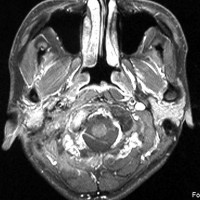

耳の聞こえと飲み込みが悪くなって発症(難聴と嚥下障害)した20代の患者さんのグロームス腫瘍 jugular paragangliomaです。左の頚動脈撮影 CAGでは,頸部の腫瘍におされて内頚動脈が前方に屈曲しています。外頚動脈から多くの血管が流入して血管腫のように濃い腫瘍陰影がみえます。右側の椎骨動脈撮影 VAGでは,頚静脈孔から頭蓋内の小脳延髄角部まで伸びた腫瘍が染まります。頭蓋内はPICAから頸静脈球と頸部には椎骨動脈の筋肉枝からの腫瘍血管がみられます。

頸部から頸静脈球を抜けてS上静脈洞内に入ります。これはクラスCかDか迷うところです。ちょっと難しい。またこのサイズでは,迷走神経と舌咽神経の機能を温存することができません。延髄方向へ伸展していますし年齢が若いので手術せざるを得ないものでした。

この腫瘍は放射線治療で制御できるものではないでしょう。手術で全摘出できて10年以上再発はありません。嚥下障害と強い嗄声が残りましたが,働いて社会生活はできています。